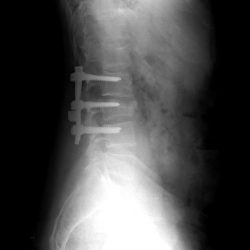

Both techniques are indicated in the treatment of vertebral fractures. Balloon Kyphoplasty is a vertebral reinforcement technique that consists of creating a cavity inside the fractured vertebra and filling it with cement, which manages to restore the height of the vertebral body. It is a minimally invasive surgical process.

Lumbar arthrodesis continues to be the surgical treatment modality most accepted in our setting for the management of discologous pain; Its purpose is to make a fixation between two or more vertebrae, requiring different implants. The main devices are: